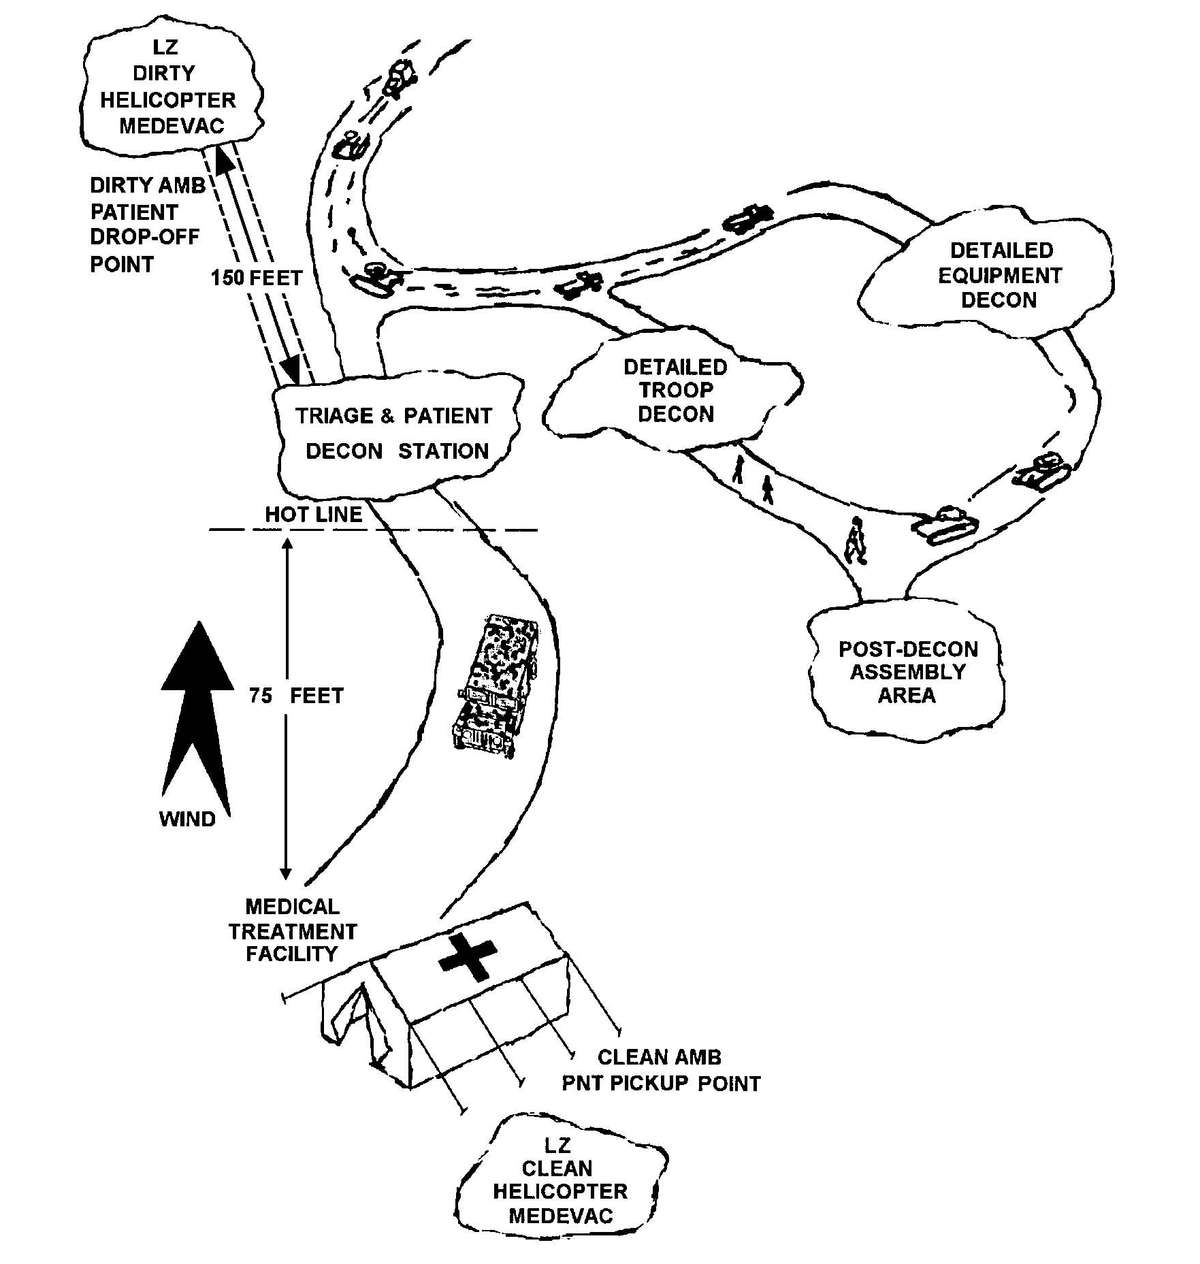

| G-3. | Patient Decontamination and Thorough Decontamination Collocation | G-2 | |

| G-4. | Patient Decontamination at the Battalion Aid Station (Level I) | G-5 | |

| G-5. | Patient Decontamination at the Medical Company Clearing Station (Level II) | G-5 | |

| G-6. | Patient Decontamination at a Hospital (Level III and IV) | G-5 | |

d. A patient decontamination station is established to handle contaminated patients (see Appendix G). The station is separated from the clean treatment area by a "hot line" and is located downwind of the clean treatment area or CPS. Personnel on both sides of the "hot line" assume a MOPP level commensurate with the threat agent employed (normally MOPP Level 4). The patient decontamination station should be established in a contamination-free area of the battlefield. However, it may be necessary to establish a patient decontamination station that is collocated with an MTF that is employing a CBPS, in a chemical vapor hazard area in order to decontaminate patients and clear the battlefield before moving the MTF to a clean area. When CPS systems are not available, the clean treatment area is located upwind 30 to 50 meters of the contaminated work area. When personnel in the clean working area are away from the hot line, they may reduce their MOPP level. Chemical monitoring equipment must be used on the clean side of the hot line to detect vapor hazards due to slight shifts in wind currents; if vapors invade the clean work area, HSS personnel must re-mask to prevent low-level CW agent exposure and minimize clinical effects (such as miosis).

b. Initial triage, EMT, and decontamination are accomplished on the "dirty" side of the hot line. Life-sustaining care is rendered, as required, without regard to contamination. Normally, the senior health care sergeant performs initial triage and EMT at the BAS. Secondary triage, ATM, and patient disposition are accomplished on the clean side of the hot line. When treatment must be provided in a contaminated environment outside the CPS, the level of care may be greatly reduced because medical personnel and patients are in MOPP Level 3 or 4. However, lifesaving procedures must be accomplished. See FM 8-285 for specific treatment of CW agent patients.

(4) The relative positions of the contaminated area, forward line of own troops (FLOT), and threat air defense systems will determine where helicopters may be used in the MEDEVAC process. One or more helicopters may be restricted to contaminated areas; use ground vehicles to cross the line separating clean and contaminated areas. The ground ambulance proceeds to an MTF with a patient decontamination station (PDS); the patient is decontaminated and treated. If further MEDEVAC is required, a clean ground or air ambulance is used. The routes used by ground vehicles to cross between contaminated and clean areas are considered dirty routes and should not be crossed by clean vehicles, if mission permits. Consider the effects of wind and time upon the contaminants; some agents will remain for extended periods of time.